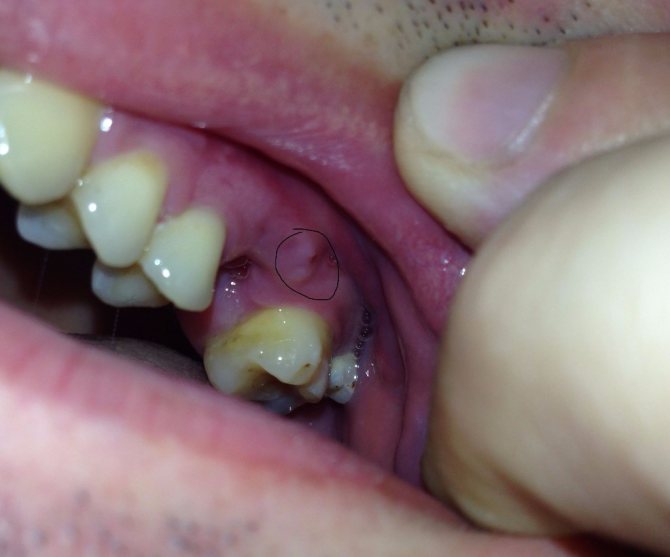

Фиброзный

Формируется из фиброзной десневой ткани с вложенными в нее костными поперечными включениями. Образуется только с вестибулярной стороны первых моляров или премоляров.

По цвету нарост совершенно неотличим от десны, при этом по форме бывает овальным или круглым с плотной консистенцией. Первоначально его поверхность ровная, но по мере его роста она обретает бугристость. Увеличиваясь, может через межзубные промежутки переходить на обратную сторону зубов.

Из всех видов разрастаний, фиброматозный имеет благоприятный прогноз лечения, растет медленно, не переходит в злокачественное состояние, безболезненный и не проявляет кровоточивости.